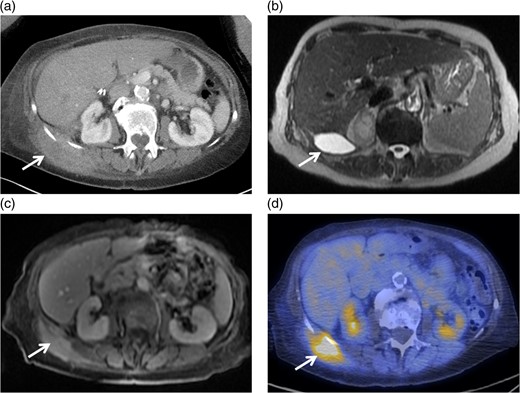

Clinical evaluation of her flank soft tissue tumor demonstrated a tender, non-erythematous, non-fluctuant 7 × 5 cm mass. Biochemical testing, including white blood cell count, was within normal limits. Computed tomography (Fig. 1a) demonstrated a 9.0 × 3.6 cm soft tissue mass and a 6.2 × 3.2 cm fluid collection abutting the right hepatic lobe and right kidney and extending into the abdominal wall. The CT findings were non specific, but the presence of a solid component with enhancing nodularity was suspicious for a neoplasm.

(a) Axial image of the CT of the abdomen with IV contrast, demonstrating a complex partially cystic, partially solid enhancing mass abutting the right hepatic lobe and right kidney and extending into the abdominal wall. (b) Axial T2-weighted sequence of the abdomen (axial T2 Single Shot Fast Spin Echo) showing the cystic component of the mass involving the right retroperitoneal space. (c) Axial T1-weighted fat saturation post-contrast sequence of the abdomen (axial T1 Liver Acquisition with Volume Acquisition after the intravenous administration of gadolinium) demonstrating enhancement of the solid component of the mass extending to the right flank musculature. (d) PET/CT showing increased FDG activity at the solid component identified on CT and MRI within the right flank musculature.

MRI confirmed the presence of a complex, partially cystic mass (Fig. 1b). The solid enhancing component extended into the right flank musculature as well as 11th and 12th ribs (Fig. 1c). Image-guided core biopsy revealed atypical spindle cells (Fig. 2a). The pathologic impression was spindle cell neoplasm, favor STS. Immunohistochemical staining revealed high Ki-67 (25%) and positive vimentin.

Positron emission tomography-computerized tomography revealed hypermetabolism (Fig. 1d) with maximum Standard Uptake Value of 13.4 g/ml. No overt metastatic spread was identified. The patient was referred for STS multi-disciplinary evaluation including discussion at Sarcoma Tumor Board. Careful review by a musculoskeletal radiologist highlighted the presence of cholecystectomy clips, fascial plane violation and round foci of calcium density (Fig. 3a and b). This raised suspicion for possible retained gallstones, especially since the violation of fascial planes was atypical for STS.